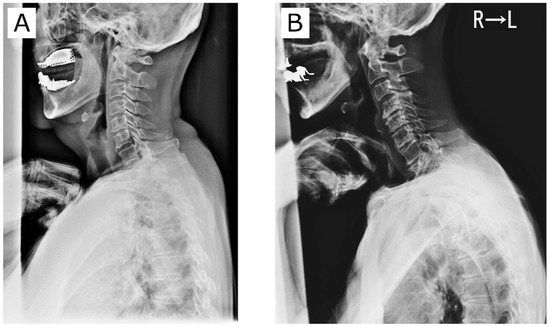

The following is a possible pathomechanism of cervical decompensation, especially in males. First, SVA and T1S increase with aging [4]. However, there is insufficient lordotic compensation due to a range of motion decrease along with a higher prevalence of cervical spondylosis [6]. This leads to decompensated axis anteriorization. The cervical spine has variable normal morphology [8]. One author reported that SVA and T1S were important in determining cervical alignment [9]. A large T1S requires a correspondingly higher CL to preserve sagittal balance. Even in cervical laminoplasty patients, T1S is one of the most important factors determining postoperative cervical spinal alignment [10,11,12]. Figure 4 contrasts representative cervical spine alignment conditions. Cases A and B had virtually identical T1S. In Case A (female), CL suitable for T1S was formed such that the position of the center of gravity of the head was optimized and the front gaze posture was preserved. On the other hand, Case B (male) had obvious cervical spondylotic change and was unable to achieve CL suitable for T1S. As a result, the head has shifted anteriorly. Based on the results of this study, the A-type cervical spine may be less susceptible to changes in subcervical alignment, while the B-type spine may tend to situate more anteriorly due to its susceptibility to subcervical alignment.

Figure 4.

Effect of cervical spondylotic changes on cervical spine alignment. Notes: Case (A) (female) has a compensated cervical spine. Case (B) (male) has a decompensated cervical spine.